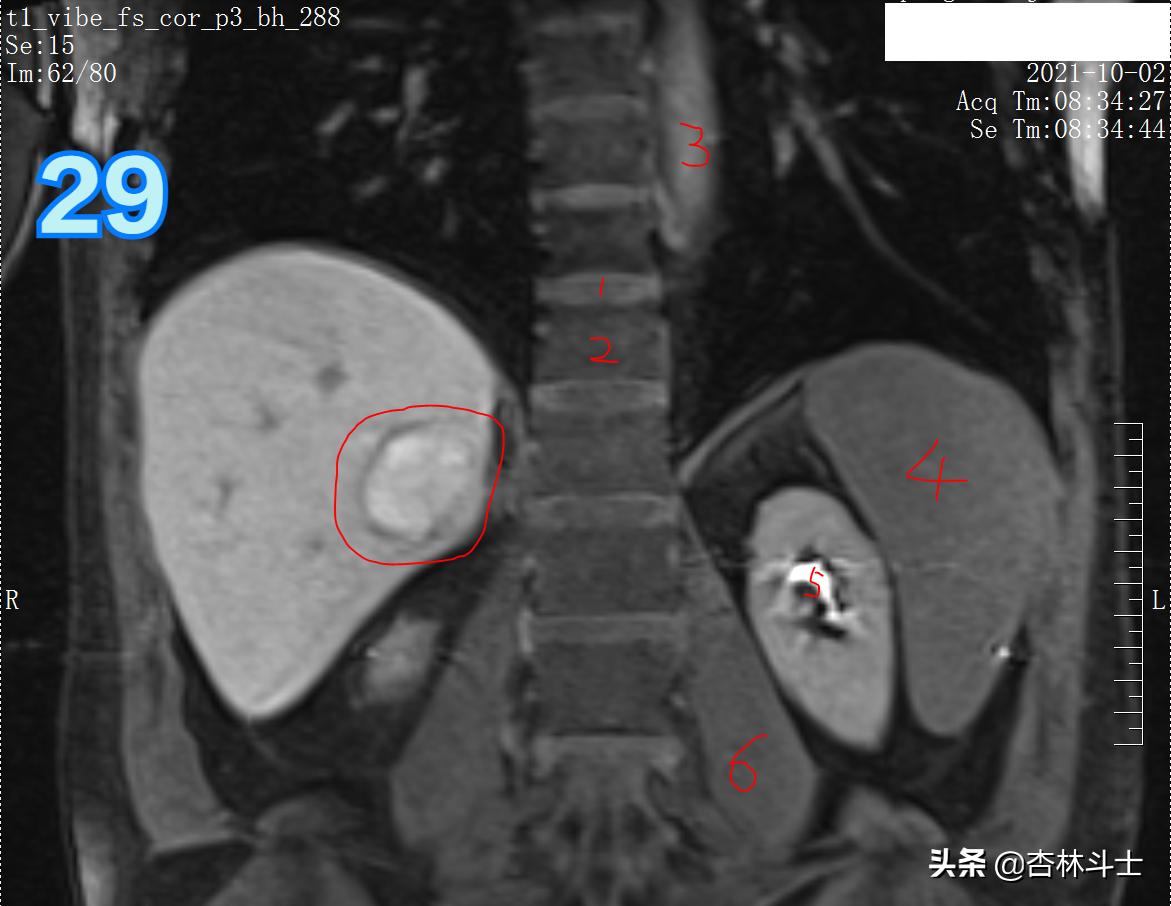

T1压脂肝胆特异期冠状位

图29 1、椎间盘 2、椎体 3、胸主动脉 4、脾脏 、肾盂肾盏 6、腰大肌

总结:10月份复查,肝右后叶下段新发一个直径约1㎝的结节,T1呈等信号,T2呈稍高信号,弥散加权序列可见弥散明显受限,增强动脉期明显均匀强化,门静脉期出现对比剂廓清,呈略低信号,平衡期信号进一步减低,肝胆特异期未见特异性对比剂摄取呈低信号。增强特征为典型的“快进快出”,影像学上典型的肝细胞癌表现。

原来那个病灶经过8个月,病灶直径明显增加(直径平均为38㎜,体积28730立方毫米,28730/5575=5.153363229)体积增加了5倍多。病灶在T1上信号略减低,强化模式未见明确改变。肝胆特异期仍显示高摄取,摄取程度较8个月前有所降低。说明病灶内OATP8表达逐渐减少。